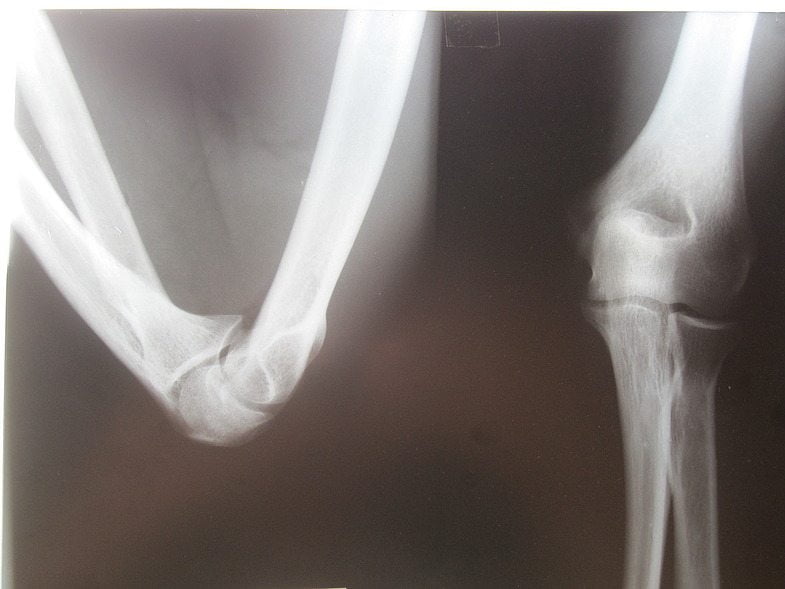

На первом прием врач осматривает пациента, выслушивает жалобы, изучает анамнез. Он измеряет амплитуду активных и пассивных движений для определения степени функциональных расстройств. Выставить окончательный диагноз позволяют результаты инструментальных исследований:

- рентгенография локтевого сустава в прямой и боковой проекциях;

- КТ или МРТ;